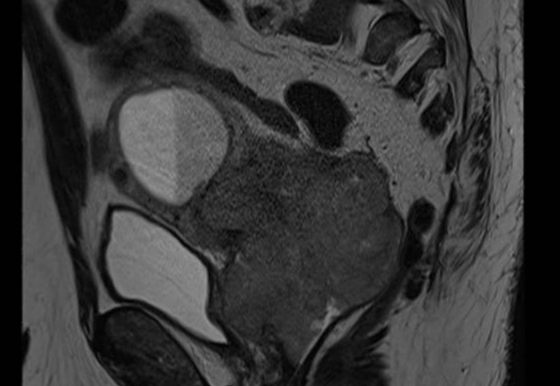

Clinical examination demonstrated a complete response, and MRI and PET imaging performed 12 weeks after treatment confirmed complete radiological and metabolic response with no evidence of residual disease.

Figure 2: Sagittal T2 MRI at 12 weeks post-treatment confirming complete resolution of cervical tumour